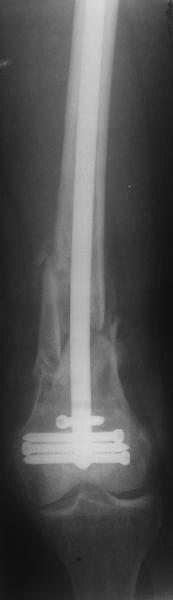

ПВ> Результат операции блокирующего остеосинтеза многооскольчатого перелома бедра.

По прямой проекции неплохо. Что за стержень?

Антеградный остеосинтез при дистальных переломах бедра мы применяем

давно, этот материал обобщен в канд. диссертации Александр

Виноградского.

Предприятие ЦИТО выпускает доработанные нами гвозди, которые хорошо

годятся для дистальных переломов, да и недороги. Можно вводть в

дистальное овальное отверстие 3 винта, которые заклинивают друг друга.

Большеберцовые стержни отлично выполняют роль ретроградных бедренных.

Конечно, которые не 9, а 12 мм в диаметре.